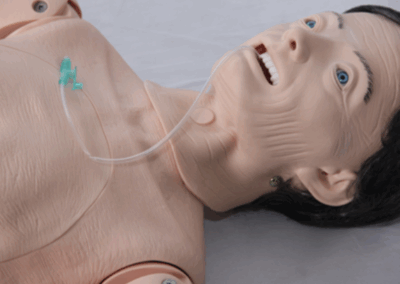

Simuladores de Diagnóstico

Equipamentos que aprimoram a capacidade de avaliação clínica.